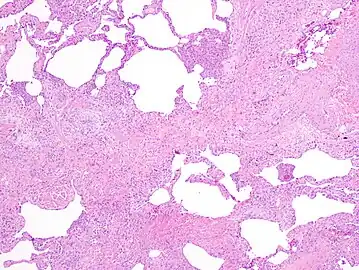

The histologic hallmarks of UIP, as seen in lung tissue under a microscope by a pathologist, are interstitial fibrosis in a "patchwork pattern", honeycomb change and fibroblast foci (see images below).[6] [7]

Appearance of usual interstitial pneumonia (UIP) in a surgical lung biopsy at low magnification. The tissue is stained with hematoxylin (purple dye) and eosin (pink dye) to make it visible. The pink areas in this picture represent lung fibrosis (collagen stains pink). Note the "patchwork" (quilt-like) pattern of the fibrosis.